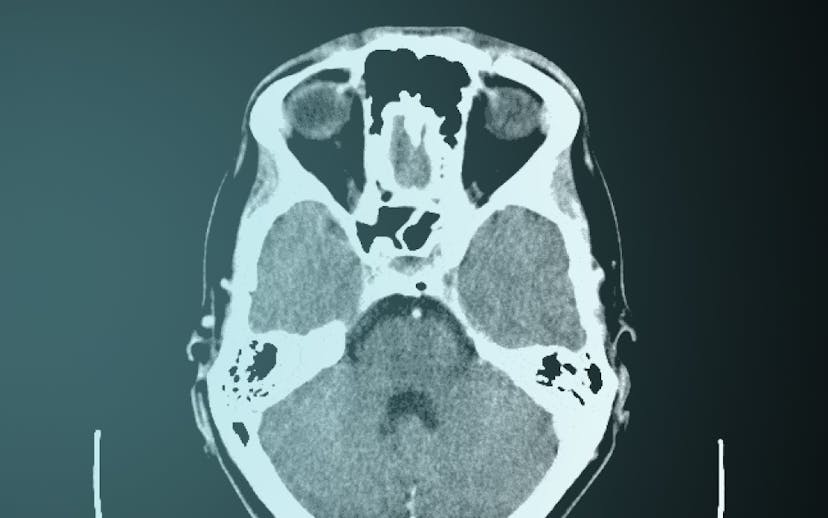

Marc Trabsky and Averyl Gaylor have co-authored a journal article for Social & Legal Studies that examines how radiological images became accepted by courts as visual evidence of death in the 20th century. Initially conceived as a speciality of photography, X-rays confounded courts, eliciting a range of judicial responses, from outright refusal to consider the images as any kind of evidence, to mocking them as cheap parlour tricks for an unwitting public, to recognising them as more reliable than the testimony of the expert witness. The article contends that courts moved towards recognising X-rays as proof of death only by both affirming forensic radiology's promise of ‘mechanical objectivity’ while acknowledging its reliance on the fallibility of ‘human subjectivity’. It suggests that this history has broader implications in socio-legal studies for comprehending how the invention of novel optical techniques continues to problematise legal epistemologies of death in the 21st century.

Post-mortem computed tomography (PMCT) has changed the experiences of bereaved people in coronial investigations. PMCT was developed by the Virtopsy® team initially at the University of Bern, but later at the University of Zurich, in the 1990s. It has been implemented in parts of Australia, Canada, Europe, Japan, UK, and USA since the early 2000s. When the technology is used as a triage tool to decide whether a medical cause of death can be found through CT scanning and an external examination of the body, it can decrease the rate of invasive autopsies in the coronial jurisdiction. For example, when the Victorian Institute of Forensic Medicine, located in Melbourne, Australia, introduced PMCT in 2005, the autopsy rate decreased by approximately 50%, and the rate of objections to autopsies by the next of kin also diminished.

Speaking before forensic scientists, Marc discussed the scope of his project on Virtual Autopsies and explained that post-mortem computed tomography has an important role in enabling coroners to meet the statutory objectives of coronial law, make recommendations for reducing the occurrence of preventable deaths, and carry out the administration of coronial justice.

Marc argued that virtual autopsies are inherently auto-optos, or to put this differently, they create the allure that judicial observers can see the interiority of the corpse with their own eyes. On the one hand, the post-mortem computed tomography appears to be more ‘objective’ than analogue technologies in determining the cause of a death. Yet on the other hand, like the images themselves which compose a body from multiple slices of data, ‘objectivity’ only takes shape through the mediation of mechanical instruments, computational techniques, and the medico-legal expert.